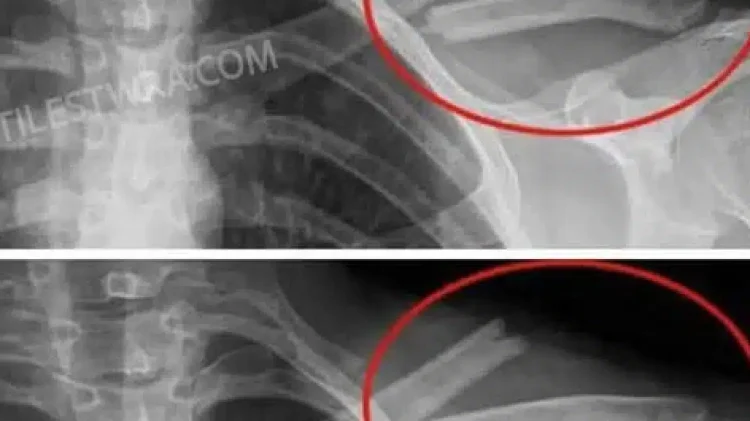

Αποδυναμώνουν τα οστά: Η υψηλή πρόσληψη νατρίου που περιέχουν πολλά από αυτά , μειώνει το ασβέστιο, αυξάνοντας τον κίνδυνο οστεοπόρωσης.